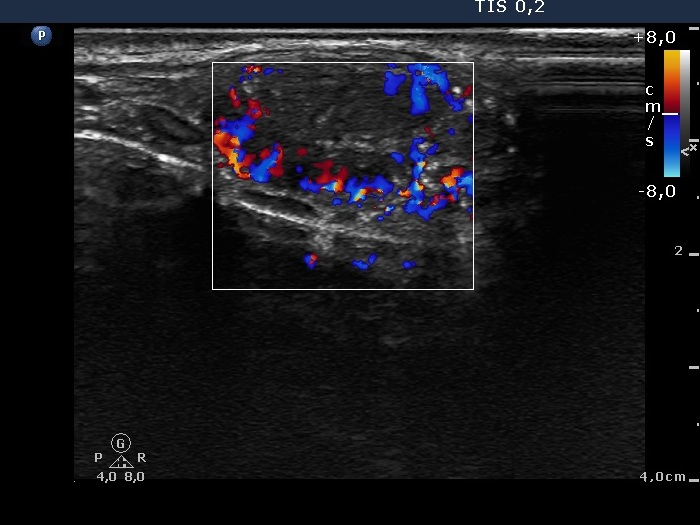

100 consecutive cases of papillary cancer - case 041 (ultrasonographic picture 5)

Left lobe, longitudinal scan, color Doppler mode. This image reveals a combined vascular pattern, the lesion has both perinodular and intranodular blood flow.